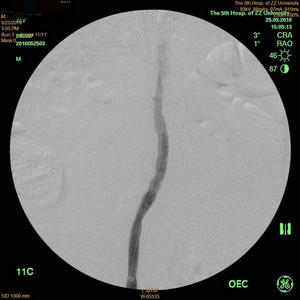

术后造影提示血管恢复通畅